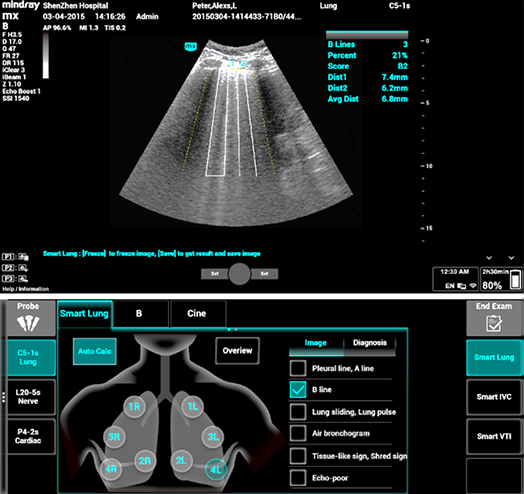

1Smart B-line

Tel automatisch het aantal B-lijnen en het percentage van de oppervlakte van B-lijnen volgens de protocollen. En scoor de prestaties van de long in vier patronen volgens de longbeluchting. Beeldoverzicht en kleurenkaart van de score kunnen helpen bij de beoordeling van de longfunctie.